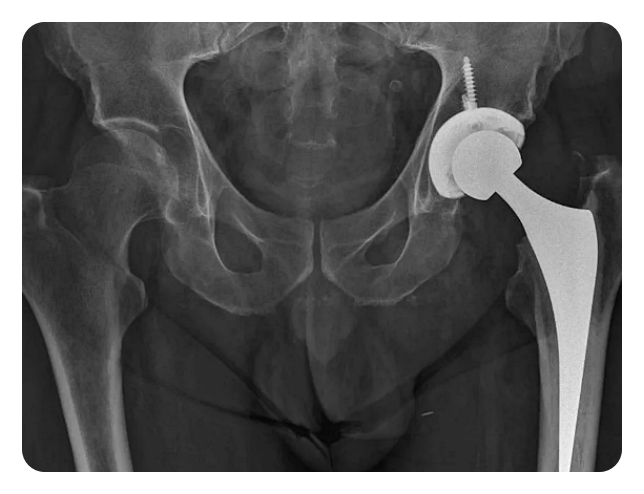

인공관절 치환술: 이 수술은 고관절이 심각하게 손상되거나 통증으로 인해 일상 생활에 지장을 주는 경우에 시행됩니다. 이 수술은 손상된 관절을 제거하고 인공 관절로 대체함으로써 이루어집니다.

영상 진단 검사는 X-ray, MRI, CT 등을 통해 고관절의 상태를 확인하고, 수술 계획을 세웁니다.